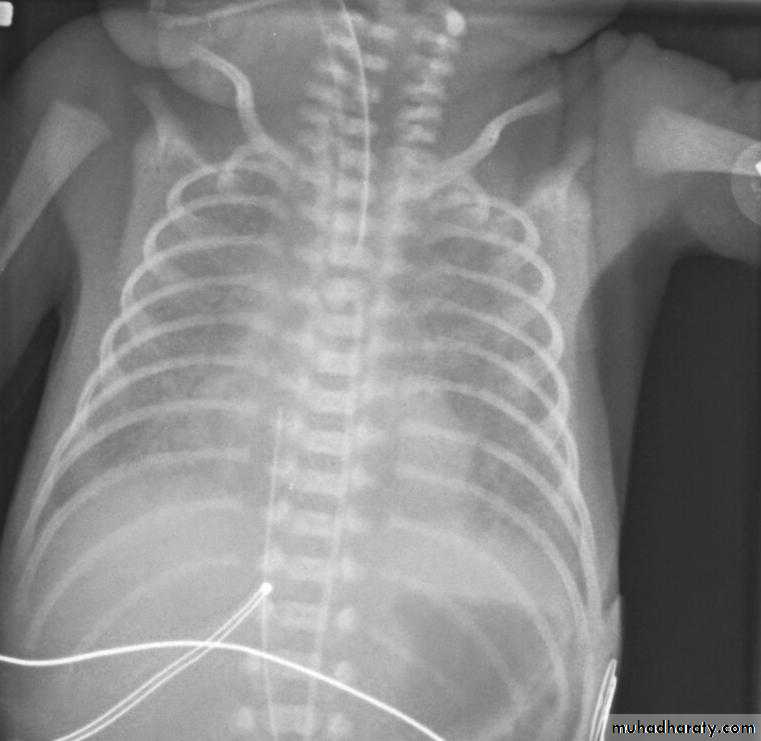

CXR shows whitening of lung with less aeration and reticular feature with ground glass appearance due to atelectases.

TTN; tansient tachypnea of newborn has mild course and its CXR shows hyperinflation and aeration and Gestational age >35+wksNeonatal pneumonia